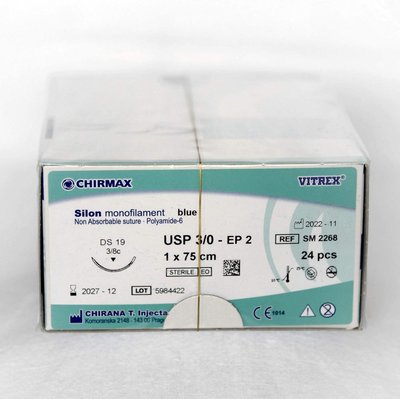

SILON monofilament nevstrebateľné šitie - modrá farba, 24 ks

CHIRANA T.Injecta

Skladem

2491 CZK

s DPH

€101.5

103.78 Kč/ks

Balení: 24 ks